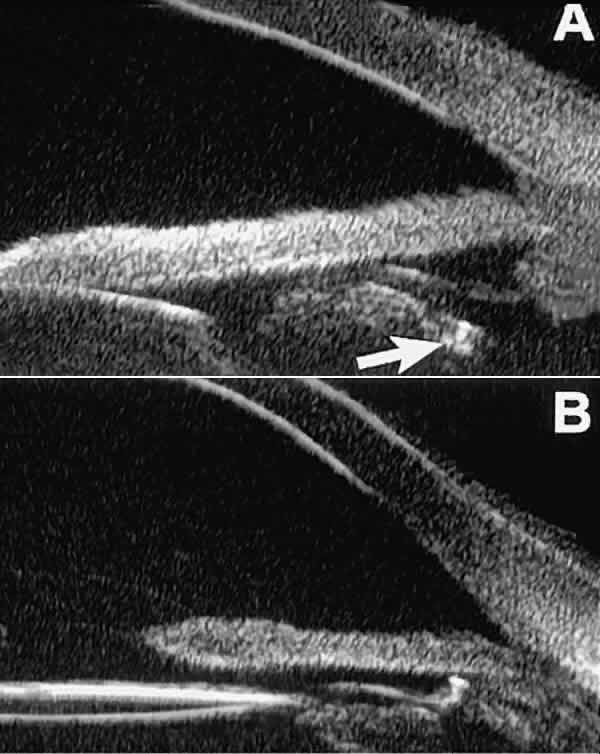

The role of UBM in the preoperative assessment of eyes with cataract is as yet unknown. In certain eyes, however, UBM may reveal features or abnormalities that could alter the ophthalmologist's surgical approach. Postoperatively, UBM can show the size and location of an intraocular lens (IOL) and the positioning of the haptics. A posterior chamber IOL appears on UBM as a highly reflective plate (corresponding to the lens optic) in the retropupillary plane with reverberation artifacts behind it (Fig. 17A). In contrast, an anterior chamber IOL appears on UBM as a sonoreflective plate located anterior to the pupillary plane (see Fig. 17B). In most eyes with a posterior chamber IOL, UBM can show whether the haptics are in the capsular bag (Fig. 18A), in the ciliary sulcus (see Fig. 18B), or in some other anatomic location12 (e.g., resting on the peripheral iris or secured with sutures to the sclera). The haptics are easier to locate if they are made of polymethyl-methacrylate than if they are made of proline because the former has a stronger reflectance.

Fig. 18 . Localization of posterior chamber IOL haptics by UBM. A. Haptic in capsular bag (arrow). B. Haptic (bright object just behind peripheral iris) in iridociliary sulcus.